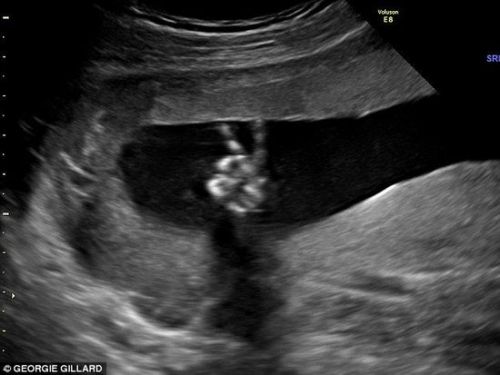

據(jù)英國《每日郵報》報道,英國一對準(zhǔn)父母在胎兒的超聲波圖像上發(fā)現(xiàn)寶寶正用小手比出“剪刀手”——V字手勢。準(zhǔn)媽媽表示,胎兒的這個手勢讓她覺得很安心。這對父母決定如果是個男孩,就給他起名為溫斯頓,因為剪刀手最早源于溫斯頓·丘吉爾,是世界和平的象征。